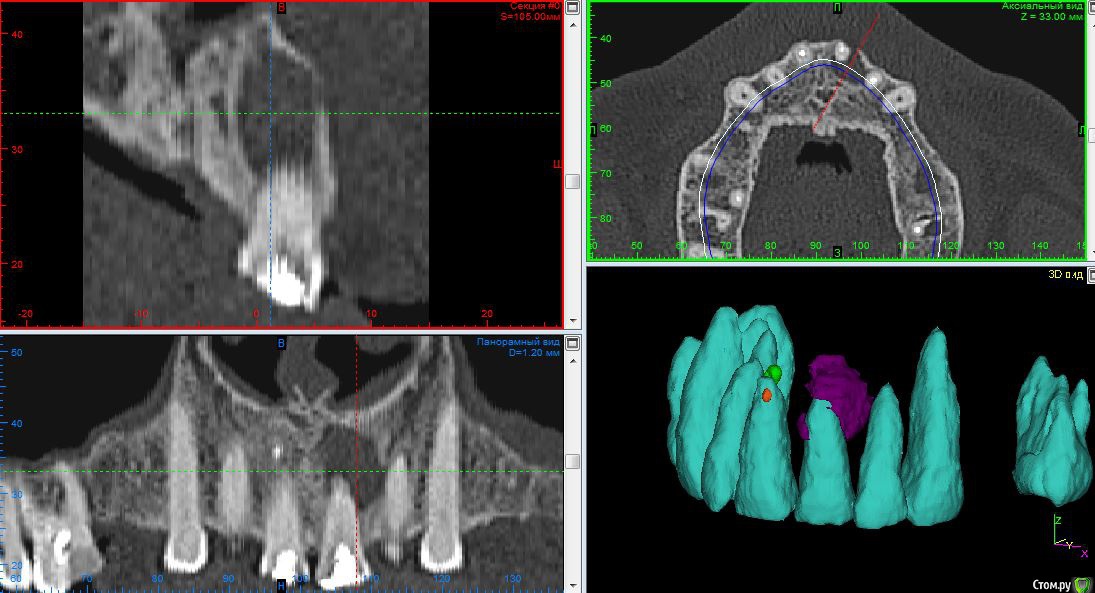

SDC Опубликовано 23 марта, 2015 Поделиться Опубликовано 23 марта, 2015 (изменено) Половина (хирурги) говорят удалять зуб, резекцию делать поздно и чтоб не слушал никого. )))Важно не то, что в кости, а объем/количество твердых тканей зуба, чтобы было, что восстанавливать, а потом улыбаться и кусать.Смотрите пример: до и после через 5 мес. В данном случае классическое ортоградное лечение было осложнено тем, что несколько лет назад уже проводилась неквалифицированная резекция верхушки корня, без ретроградной пломбировки, но тем не менее. Я думаю, еще полгода и произойдет полное восстановление костной ткани. http://s43.radikal.ru/i099/1503/57/48b064b4ee70.jpg http://s017.radikal.ru/i441/1503/e5/58c23524bac9.jpg Изменено 23 марта, 2015 пользователем SDC Ссылка на комментарий